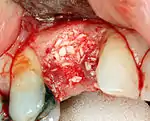

Hard tissue (bone) reconstruction

Bone grafting is necessary when there is a lack of bone. Also, it helps to stabilize the implant by increasing survival of the implant and decreasing marginal bone level loss.[40] While there are always new implant types, such as short implants, and techniques to allow compromise, a general treatment goal is to have a minimum of 10 mm (0.39 in) in bone height, and 6 mm (0.24 in) in width. Alternatively, bone defects are graded from A to D (A=10+ mm of bone, B=7–9 mm, C=4–6 mm and D=0–3 mm) where an implant's likelihood of osseointegrating is related to the grade of bone.[41]: 250

To achieve an adequate width and height of bone, various bone grafting techniques have been developed. The most frequently used is called guided bone graft augmentation where a defect is filled with either natural (harvested or autograft) bone or allograft (donor bone or synthetic bone substitute), covered with a semi-permeable membrane and allowed to heal. During the healing phase, natural bone replaces the graft forming a new bony base for the implant.[37]: 223